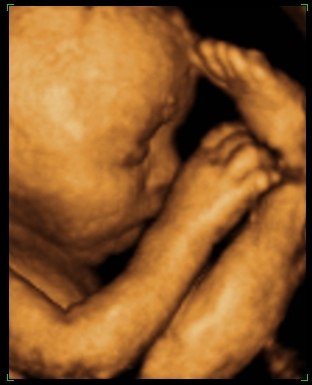

så var vi til 3D scanning i fredags. Så vild en oplevelse.. Hun er bare helt perfekt.

hun vejede 1423g, og så var hun en uge foran så det var da super dejligt at vide at lille pigen har det super og lever luxus derinde i maven

vi var heldige med at hun var rigtig aktiv plus vi også så hende med åbne øjne

Vedhæftede fotos (klik for at se i fuld størrelse)